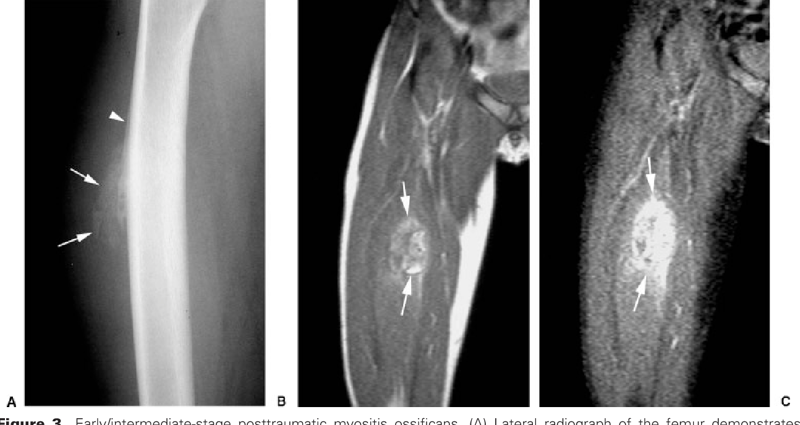

В первую очередь Юлиус пытается сравнить болезнь с Myositis ossificans circumscripta – схожим феноменом доброкачественных неопухолевых костных образований в мышцах и мягких тканях. Сегодня считается, что MОС, или оссифицирующий приобретенный миозит, имеет травматическую причину и более точное современное его название – myositis ossificans traumatica. Хотя механизм заболевания является загадкой, 80% появления «окаменелостей» в мышцах, преимущественно бедер и рук, являются последствием именно физической травмы. В отличии от фибродисплазии, эти камни единичны и не разрастаются так обширно. Хотя в некоторых случая межреберные пространства и грудные мышцы замещаются костной тканью в достаточно больших объемах. Возможно, вам это покажется отсылкой на суперспособности, когда после сильной травмы вы становитесь сильней, а ваши кости крепче. Что ваши ребра срастаются вместе, утолщаются за счет окостенения мышечной ткани и создают вам бронежилет, делающий вас неуязвимыми. Ну что же… это не так. Вообще, фраза о том, что сломанные кости становятся крепче, может звучать только от тех, кто их не ломал, а потом не сидел, обняв кота в свои 50 лет в дождливый вечер у окна. Реальность очень и очень далека от таких мифов, заключающихся в инвалидности, ограничении подвижности, проблемам с позвоночником и болями, в сравнении с которыми ваша межреберная невралгия даже рядом не стоит.

Костное образование в мышце на ноге:

Розентрин тоже не знал, почему так происходит. Единственная разница между нами и ним в том, что мы лучше знаем механизм образования костей и отличаем его от кальцинирования. Сегодня мы знаем, что при повреждении скелетной мышцы высвобождаются воспалительные цитокины – важные гормоноподобные белки. Эти белки, помимо иммунной системы, стимулируют эндотелиальные клетки кровеносных сосудов. Эндотелий в норме синтезирует множество веществ, регулируя огромный ворох функций – от артериального давления до проникновения воды, продуктов метаболизма в кровь и обратно – являясь не просто стенками вашей кровеносной системы, как полиэтиленовый пакетик, а живым регулятором, фильтром и средством контроля многих функций. Резкий выброс цитокинов заставляет клетки этого эндотелия превращаться в мезенхимальные стволовые клетки, что в большинстве случаев поможет вам восстановить повреждения. Но иногда что-то идет не так, и М.стволовые клетки дифференцируются на хондроциты и остеобласты. Остеобласты в организме формируют костную ткань, и если они появились, а все кости давно сформированы, они иногда могут начать формировать новую кость в том месте, где ей вовсе не место.